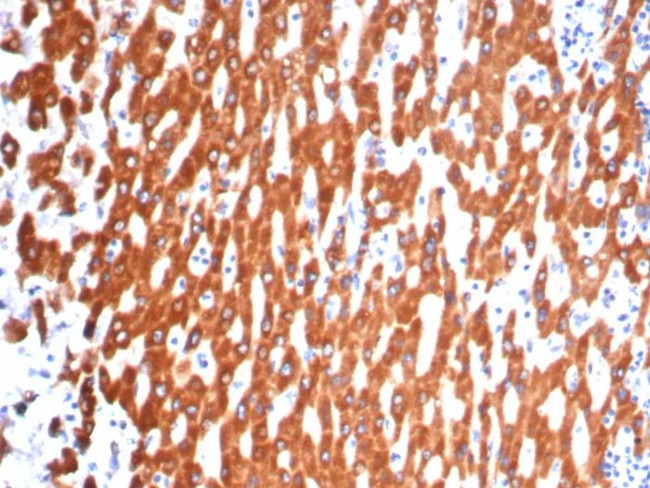

Positive Control:Human heart or adrenal gland. Stimulated peritoneal macrophages.